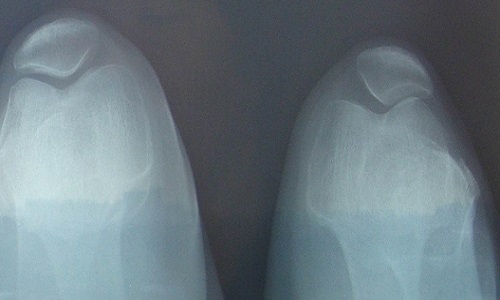

患者完全没有症状,未意识到有杵状指。在出现杵状指之前即有明显的慢性骨骼疼痛,以酸痛为主,部位较深,常不能明确指出具体部位,无法坚持工作。杵状指为最突出的临床表现之一,指(趾)端呈球状正常的甲周160度角度减小,手指在甲床基部厚度超过远端指间关节的厚度,甲床基部周径大于远端指间关节的周径。由于甲床软组织增生和水肿,指甲触诊有一种“摆动感”。晚期皮肤增厚,指甲变弯,发绀,产生鼓槌样畸形。部分患者手足增粗变厚,长度不增加而呈铲状或兽掌状。

约半数患者出现关节疼痛肿胀、关节积液。以膝踝关节受累多见,尚可累及肘腕、掌指关节和跖趾关节,一般呈不对称性,疼痛以夜间为主,表现为关节轻度酸痛乃至剧烈疼痛。体征包括关节局部发红、发热、触痛肿胀、关节积液和活动受限,也有表现为无痛性关节积液。在没有大量肌肉复盖的部位,由于长骨骨膜新骨形成,可致前臂或小腿日益增粗,腕及踝关节亦相应粗大。